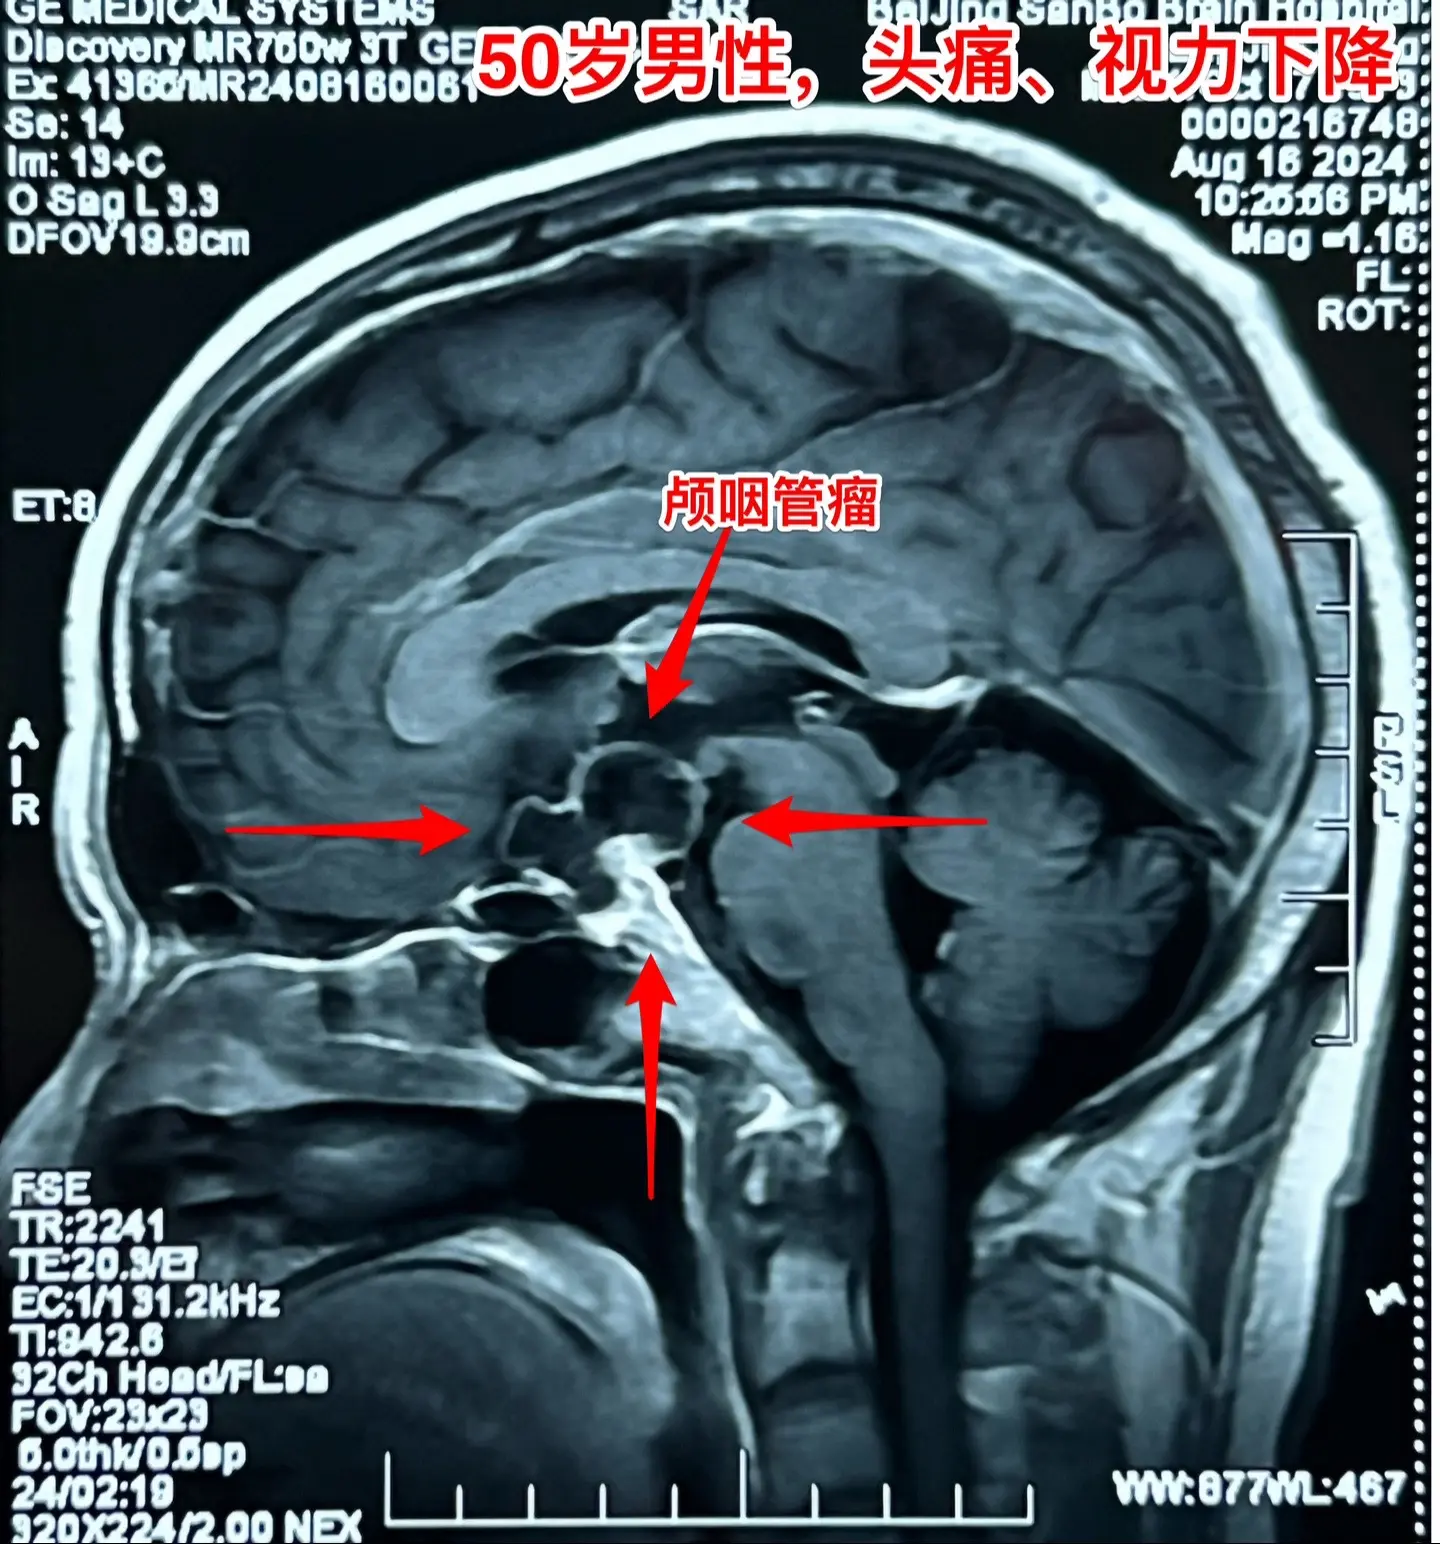

颅咽管瘤手术,出院3天就开车,合适吗?50岁的山东临沂男性,因头痛一年...